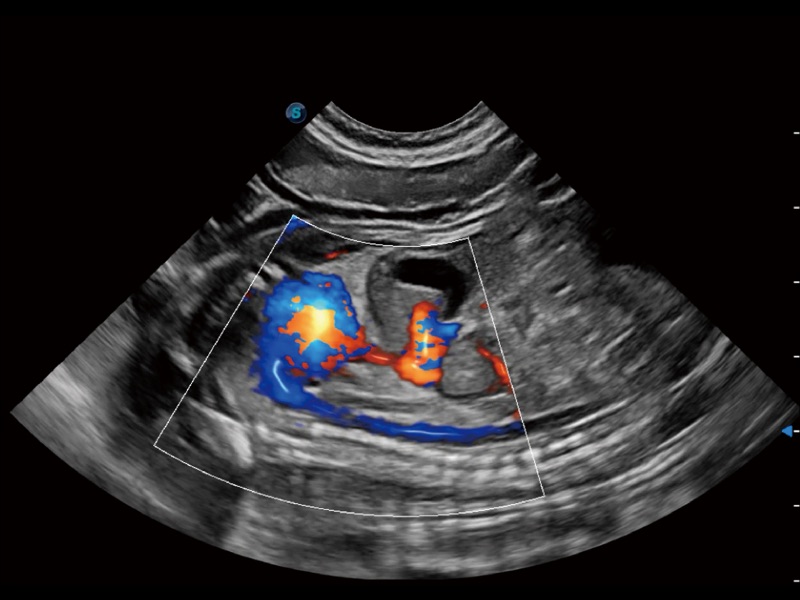

• Micro F 显微血流成像

通过创新的 Matrix E自适应滤波器和超长时间域算法,极大提升超低速微细血流的检出能力,同时更精准地滤除软组织和噪声信号,为兽用医生提供以往无法通过常规血流获得的疾病诊断信息。

• 宽景成像

通过色彩血流和实时宽景相结合,可观察到完整的静脉或动脉的血流,方便医生检查。实时扫查过程中,如有任何操作失误也可以很容易地进行回扫擦除,而不会中断扫查。

(犬)左室长轴血流

(犬)髂动脉血流

(犬)胎儿主动脉弓立体血流